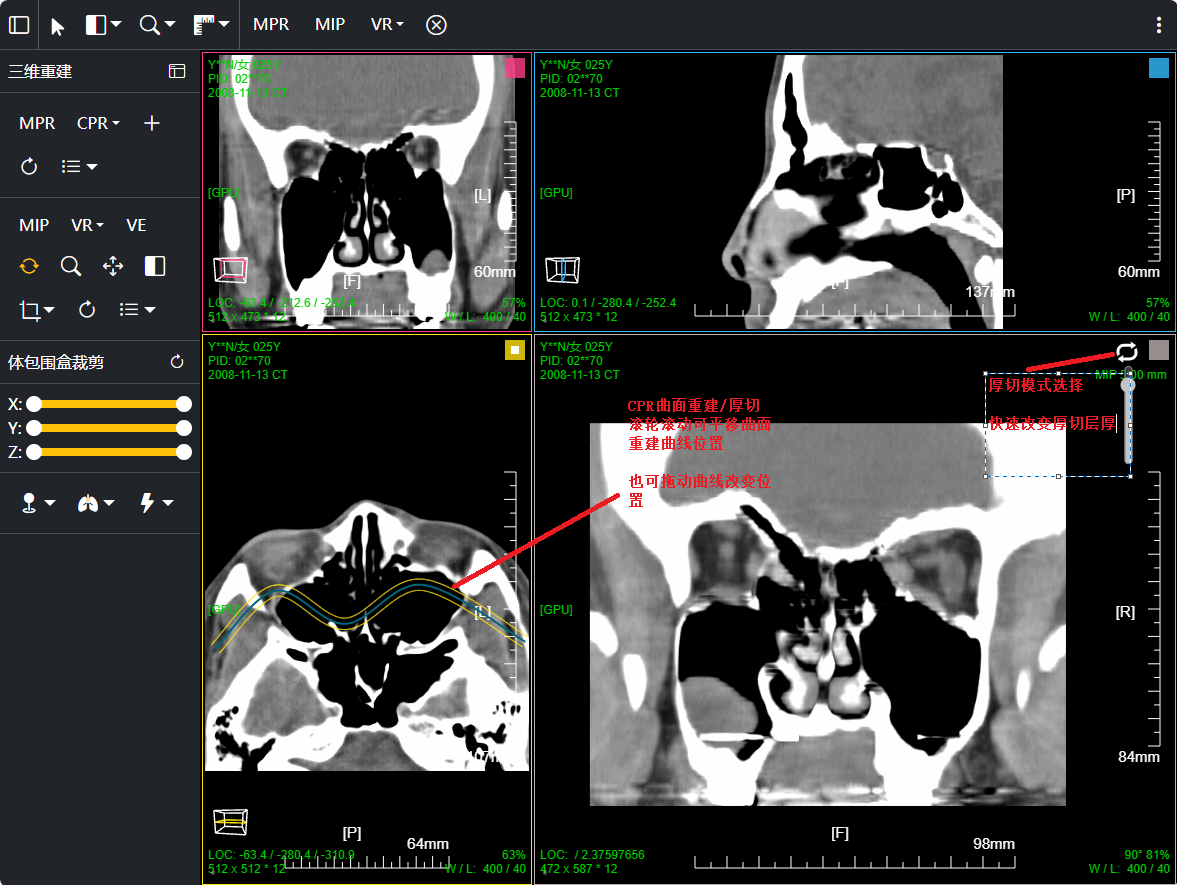

八、三维浏览功能操作和截图

左键双击MPR窗口可在MPR三窗口和1x1窗口间切换;三维渲染窗口左键双击在在1x1视图模式和当前视图模式切换

点击MPR窗口右上角颜色块可AXIS轴位、CORO冠位、SAGI矢位切片切换

鼠标右键点击MPR窗口左下 切片位置指示器 可显隐十字交叉线; 左键点击MPR复位

鼠标左键点击MIP窗口左下 三维旋转状态指示器 可快速旋转到指定面; 右键点击三维旋转复位

厚切支持MIP最大密度 、MINIP最小密度、AVG均值密度、以及VR渲染

改变厚切层厚:1、预设层厚菜单(可配置) 2、拖动滑块快速改变 3、拖动十字交叉线上的层厚虚线

CPR曲面重建 、厚切曲面;